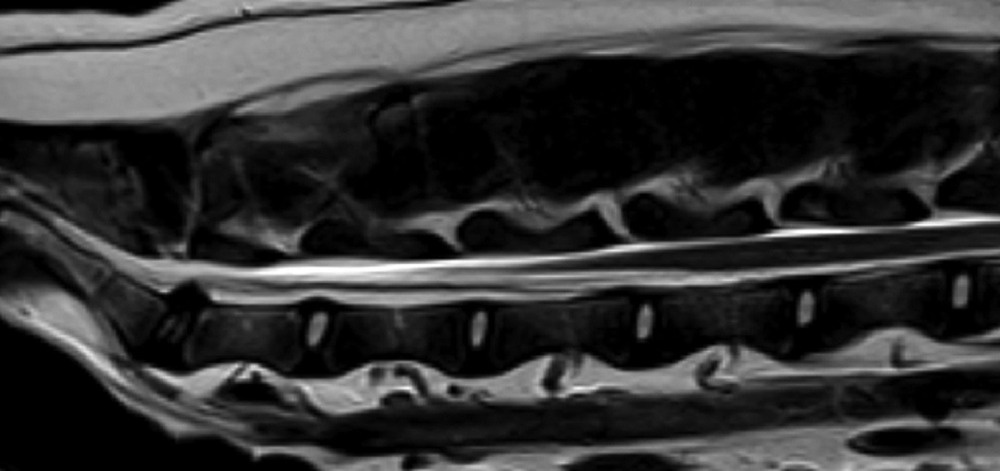

X-rays versus CT, MRI, and myelography

X-rays can help identify fractures, vertebral changes, and some patterns of disc mineralisation. However, they do not directly show the spinal cord, and they are not a reliable way to confirm or rule out IVDD on their own.

CT and MRI provide a much clearer view of the spine and the tissues around it. Myelography (a contrast study around the spinal cord) is sometimes used as well, especially in surgical planning. Your vet will talk you through what each test can and cannot answer in your dog’s case. 5, 6